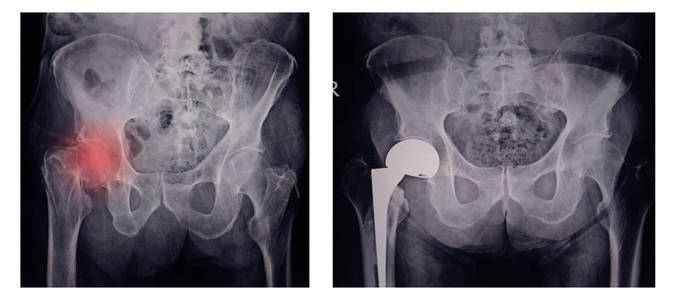

可疑髖部骨折 為什麼首選mri 而不是ct 壹讀